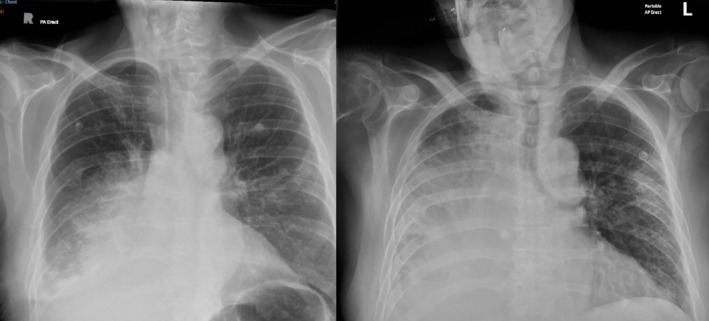

Pulmonary artery pseudoaneurysms (PAAs) are exceedingly uncommon. It is a life-threatening diagnosis, and often associated with poor long-term prognosis. We report a case of PAA in a 74-year-old man presenting with severe respiratory failure and haemoptysis with a history of advanced lung cancer. Though the intent was to manage the PAA with coil embolisation, this was unsuccessful and the patient passed away 72 h after hospital admission. There is limited evidence for treatment of PAA, and once a patient is symptomatic, has a high mortality.